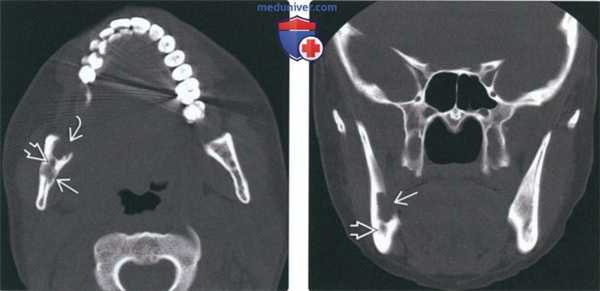

(Слева) На аксиальной КТ в костном окне у этой же пациентки визуализируется очаг в ветви и отдельно лежащий очаг спереди от него, хуже отграниченный и с более выраженной деструкцией. Между очагами визуализируется нижнечелюстной канал.

(Справа) На корональной КТ в костном окне у этой же пациентки определяется деструкция язычной кортикальной пластинки, обусловленная очагом большего размера. Обратите внимание на нижнечелюстной канал внизу. В этом случае имеет место моно-стотическая эозинофильная гранулема с изолированным поражением ветви справа: прогноз благоприятный.